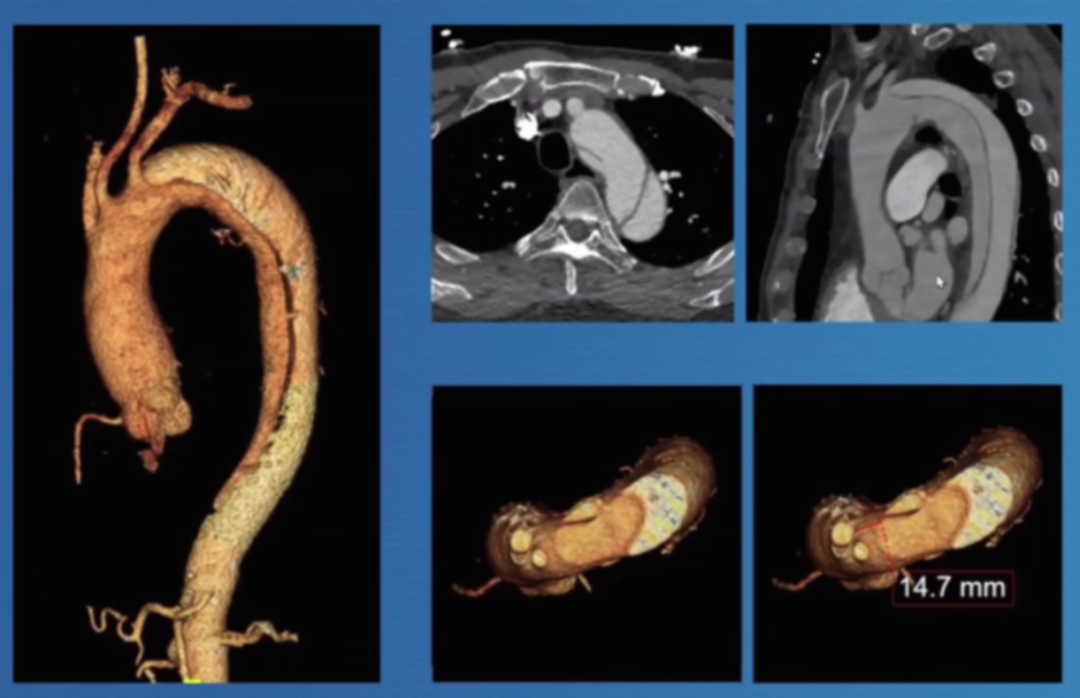

香港玛丽医院分享了38例主动脉弓分支支架植入病例的经验,其中28例为A/Br型,8例为B/Br型,1例为L型,患者平均年龄75.5岁,男性34例。30天死亡率为7.8%,手术中风率10.5%(2例严重+2例轻微),再干预率21%,逆行夹层3例,动脉瘤相关死亡2例。

在主动脉介入治疗领域,支架设计持续创新。Terumo双分支支架采用大型矩形凹槽设计,即便旋转90度,仍能顺利接入分支,对于弓部曲线较为紧张的情况适配性更强。不过,该支架也面临技术挑战,手术中需要精准控制支架的旋转与对齐,以确保治疗效果。

深圳设计的支架同样亮点十足。它具有短输送尖端的特点,无需跨越主动脉瓣,部署过程简单,且不需要进行严格的血压控制。支架配备两个平行侧支,搭配低剖面8-9F桥接支架,在接入方式上,采用右臂入路结合左颈动脉小切口的方式,为手术操作提供了便利,也有望为患者带来更优的治疗体验。